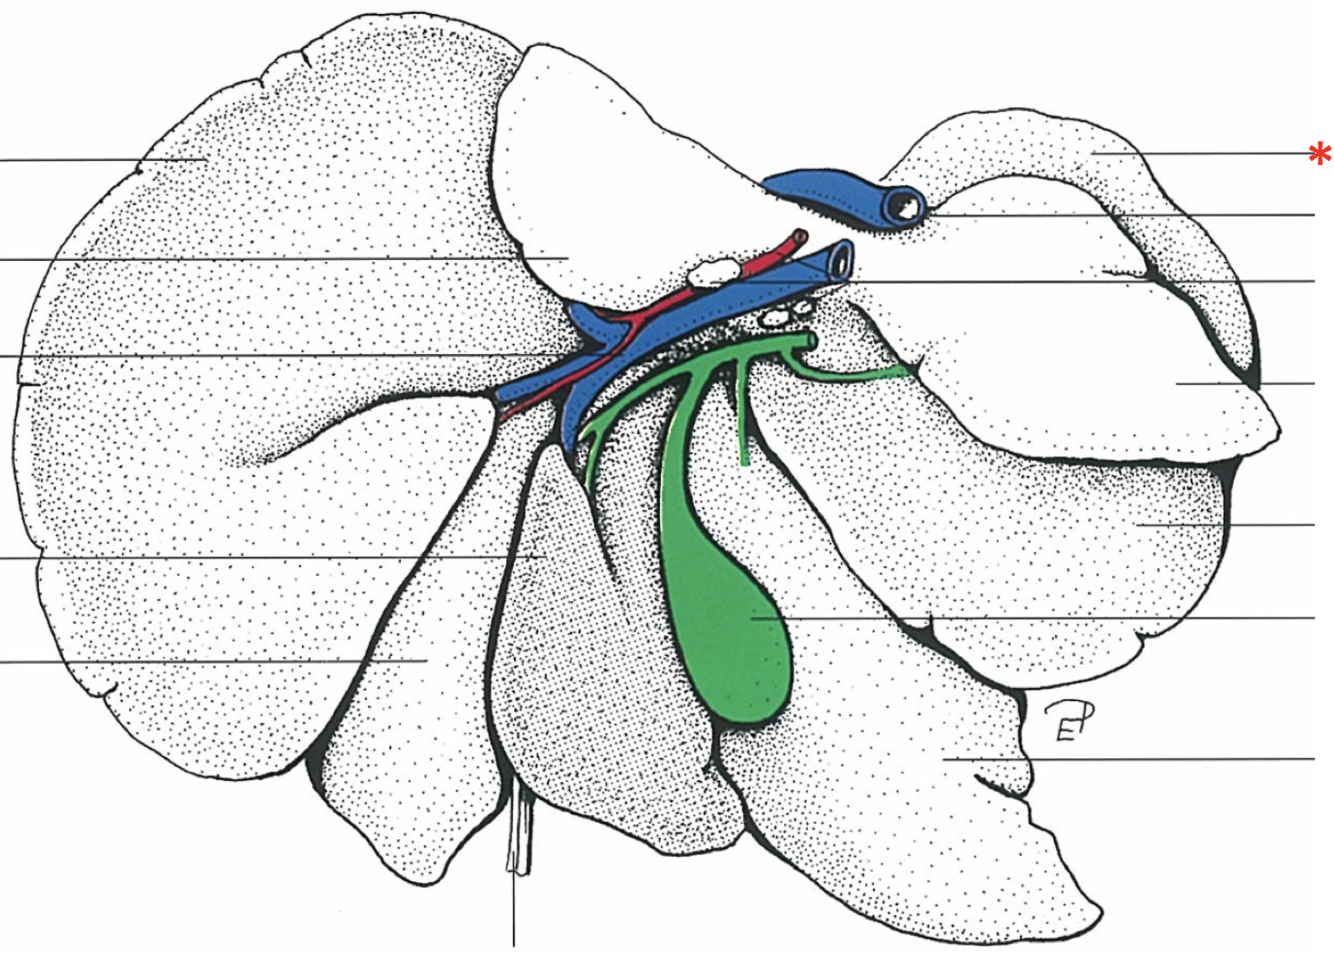

What is shown? Give the Aspect.

Liver of a Cat

Facies diaphragmatica

Dorsal Aspect

Area nuda

- Not covered by serous membrane

The Caudate Process extends from the…

Lobus caudatus

The sharp-edged border of the liver is called…

Margo acutus

The blunt-edged border of the liver is called…

Margo obtusus

Ligg.falciformehepatiset tereshepatis

18

Lig. coronale hepatis

15

Lig. triangulare sinistrum

Lig. triangulare dextrum

Lig. hepatorenale